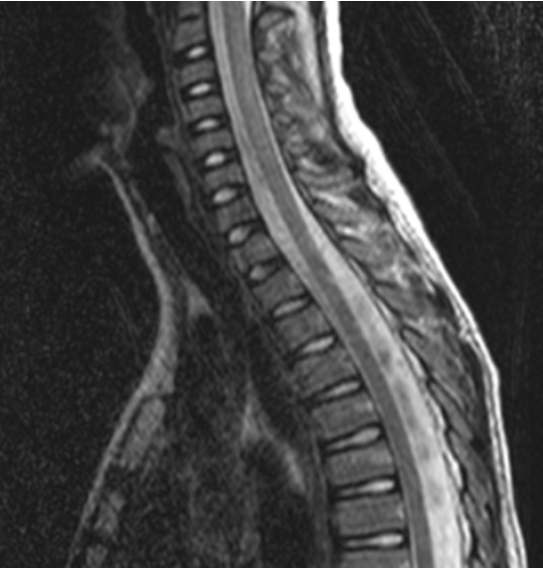

化学位移伪影由于人体中水和脂肪内氢质子进动频率差异所致,常出现在水/脂界面,可能被误认为硬脊膜结构。

此外,还有其他容易识别的伪影。骨科金属植入物在高场强时会引起更广泛伪影,表现为低信号强度和脊髓变形。外周信号伪影因线圈单元与扫描范围不匹配产生,有多种表现形式。拼接伪影在脊柱扫描拼接中,因金属异物、参数不一致等因素,导致上下两段对比度不一致。同时,阅片时还需注意不要忽略正常解剖结构,如椎基静脉孔和神经血管脂肪簇等。